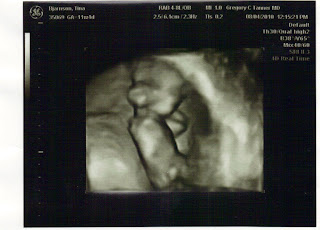

A 3D picture of our baby. It's covering It's ears. You can see that its arm is bent.